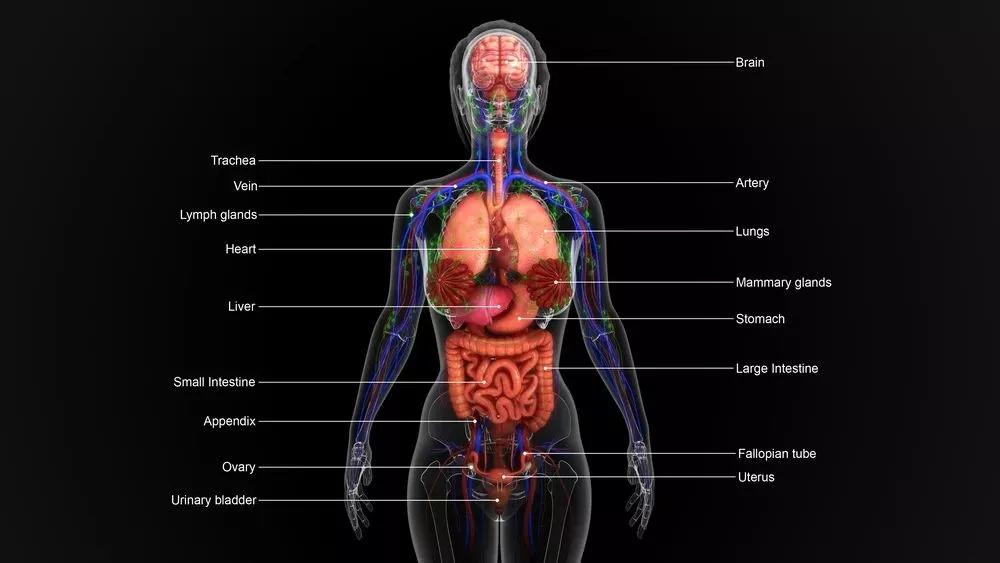

1、人体8大器官最不抗冻

寒潮来袭,羽绒服、围巾、帽子等御寒神器几乎人手必备。除了鼻子、耳朵、双手这些露在外面的部位,一些看不见的器官同样需要保暖。

01 血管:遇冷收缩易变脆

寒冷刺激造成心脏收缩力增强,周围血管收缩,导致收缩压及舒张压上升,易导致脑出血、脑梗塞等。

02 心脏:最怕温差大

室内外温差大,心脏负荷增加,严重时引发粥样硬化斑块破裂、血管堵塞,造成心绞痛或心肌梗死。

03 肺部:容易落下病根

冬季寒冷、干燥的空气,都要经过“肺”这个气体交换站进入体内。寒冷空气容易引起咳嗽、胸闷,甚至哮喘、呼吸困难等问题。

此时不加以保护,不仅会诱发咳嗽等一些呼吸道疾病,还非常容易落下病根,导致来年复发。

04 肠胃:代谢会变慢

穿衣过少和吃寒凉食物易受凉,导致胃部肌肉、血管收缩,发生胃痉挛。

天气变冷,胃本身也会有些倦怠,如果食用过冷、过生、过硬的食物,会给胃带来额外的负担。

05 鼻子:防止病菌从鼻入

冬天鼻黏膜直接接触冷空气,其黏液分泌减少,毛细血管变脆,鼻子的“屏风”作用也容易变差,从而导致有病菌的空气直接进入肺内,增加了呼吸道感染的几率。

06 关节:容易受伤

气温较低时,血管收缩,肌肉和韧带柔韧性较差,对关节的保护减弱,容易造成关节损伤及摔伤骨折。

07 耳朵:抗冻能力最差

朵除了耳垂部分有脂肪组织能保温外,其余部分只有较薄的皮肤包着软骨,所以是五官中最“怕冷”的器官。耳朵容易长冻疮,其实就是怕冷的表现。

08 前列腺:也会“感冒”

受凉时容易出现尿频、尿急、尿痛、排尿不尽、尿无力、会阴部及小腹疼痛不适等症状。